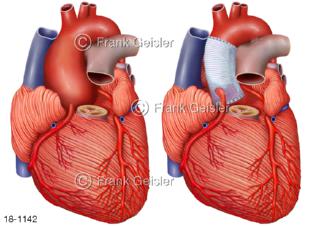

18-1142 Krankheitsbild Aorta Herz mit Aneurysma Aortenaneurysma, Platzierung Gefäßstütze Stent